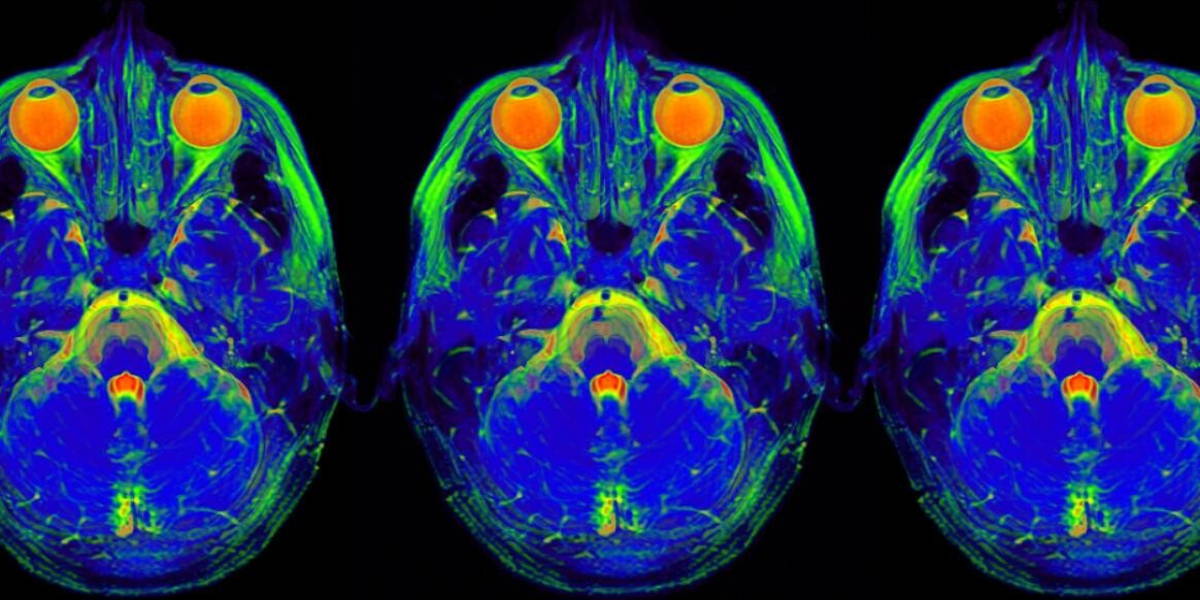

These tools enable quantitative analyses of radiological images taken from patients suspected of having ischemic stroke, writes the AMC in a press release. The value of these tools has been recognized worldwide with requests to utilize them in a wide range of studies and research groups. The portfolio was developed as part of the successful MR CLEAN trial.